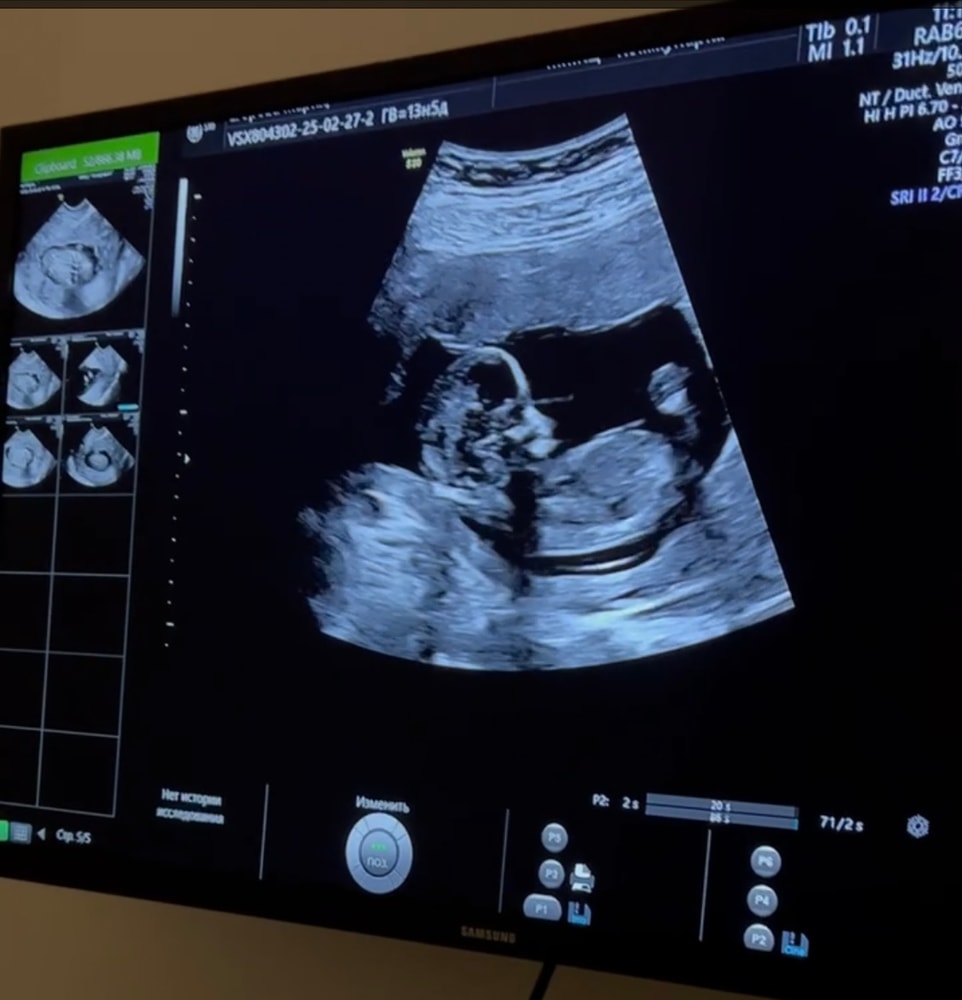

Вот и 22 недели 👀

Наши будни, наши неделькиПросто отметка для себя, вот уже и 22 недели по узи, как пишут, первый маленький ребенкин рубеж достигнут.

Пол до сих пор не знаем точно, только предположение с 1 скрининга на девочку, но через пару недель для себя ещё сходим на узи, может к Пятых смогу попасть. А то на 2 скрининге даже фото не дали🙄 Но муж уже по имени обращается, как к девочке 😁